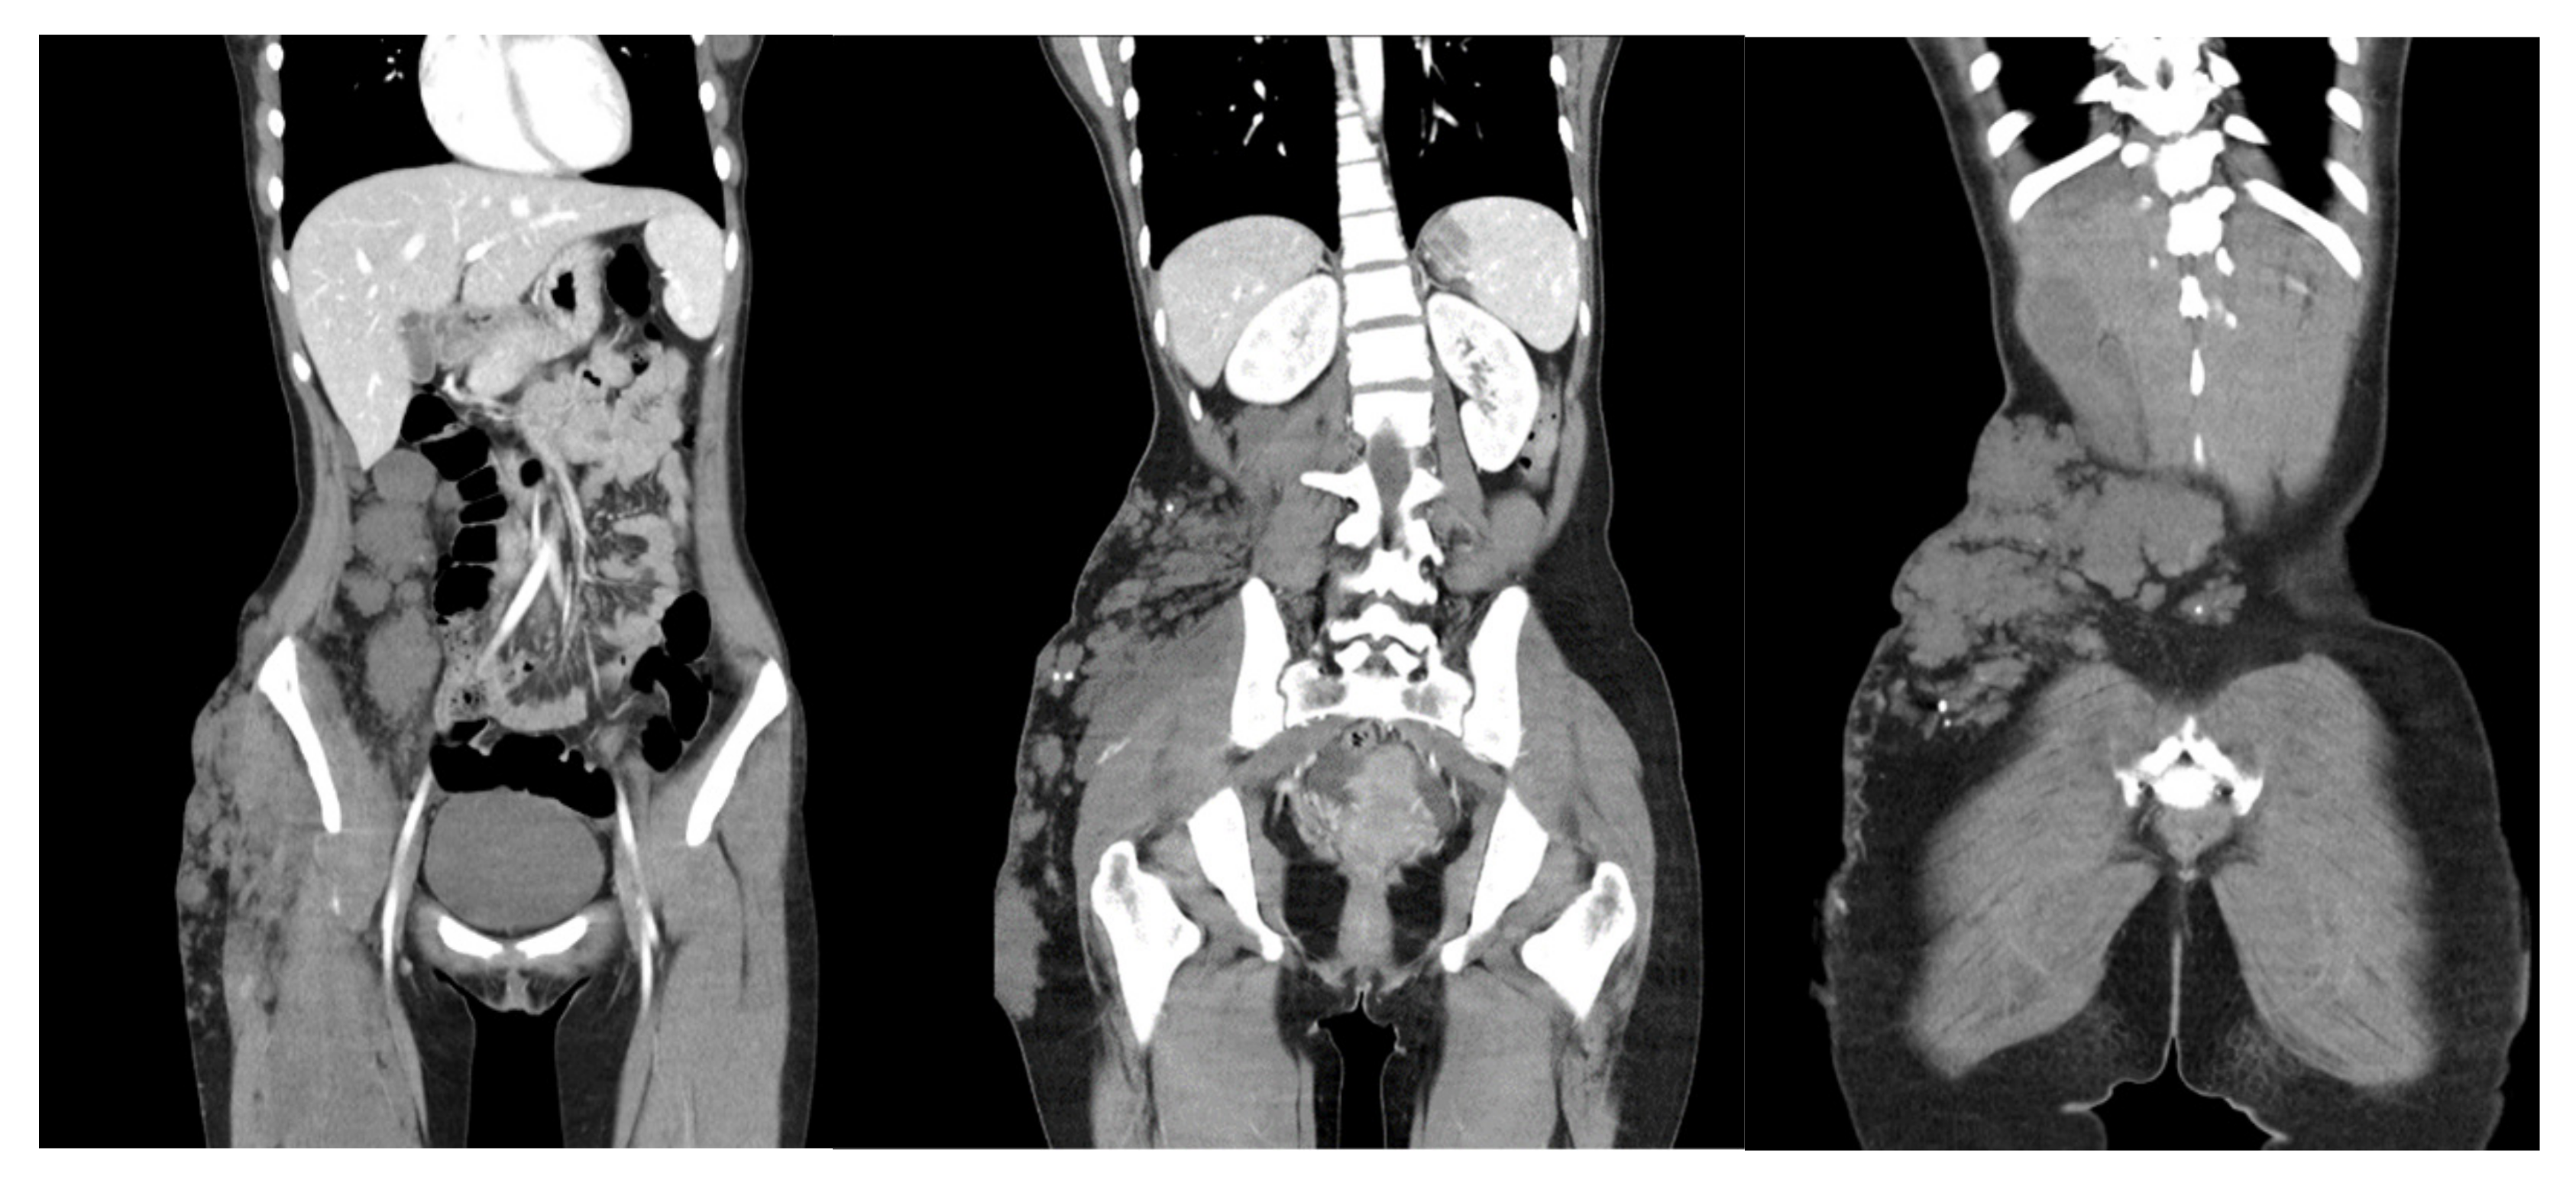

A 17-year-old girl presented with unilateral hypertrophy of the right lower limb and the lower back with tumefactions of 7.0 cm to 25.0 cm long, composed of grouped blue blebs (Figure 1). The lesion was present since birth and gradually increased in size. She was taking iron supplements for persistent asymptomatic iron deficiency anemia. Otherwise, no systemic or developmental defect was noted. Results of abdomen and pelvis computed tomography (CT) showed extensive unilateral soft tissue masses with macrocalcifications along the intramuscular and subcutaneous regions of the right lower back, buttock, and the anterolateral portion of the proximal thigh (Figure 2). Venous malformations and splenomegaly with multiple small vascular malformations were also noted. Endoscopy revealed nodular gastritis and colonoscopy showed normal findings. From the findings, a diagnosis of atypical KTS was made.

Figure 2.

Abdominal and pelvic CT shows unilateral soft tissue hypertrophy with calcifications on the right side of the lower abdomen, lower back, buttock, and proximal thigh. Venous malformation in the right gluteal muscle and splenomegaly with multiple small vascular malformations were observed.